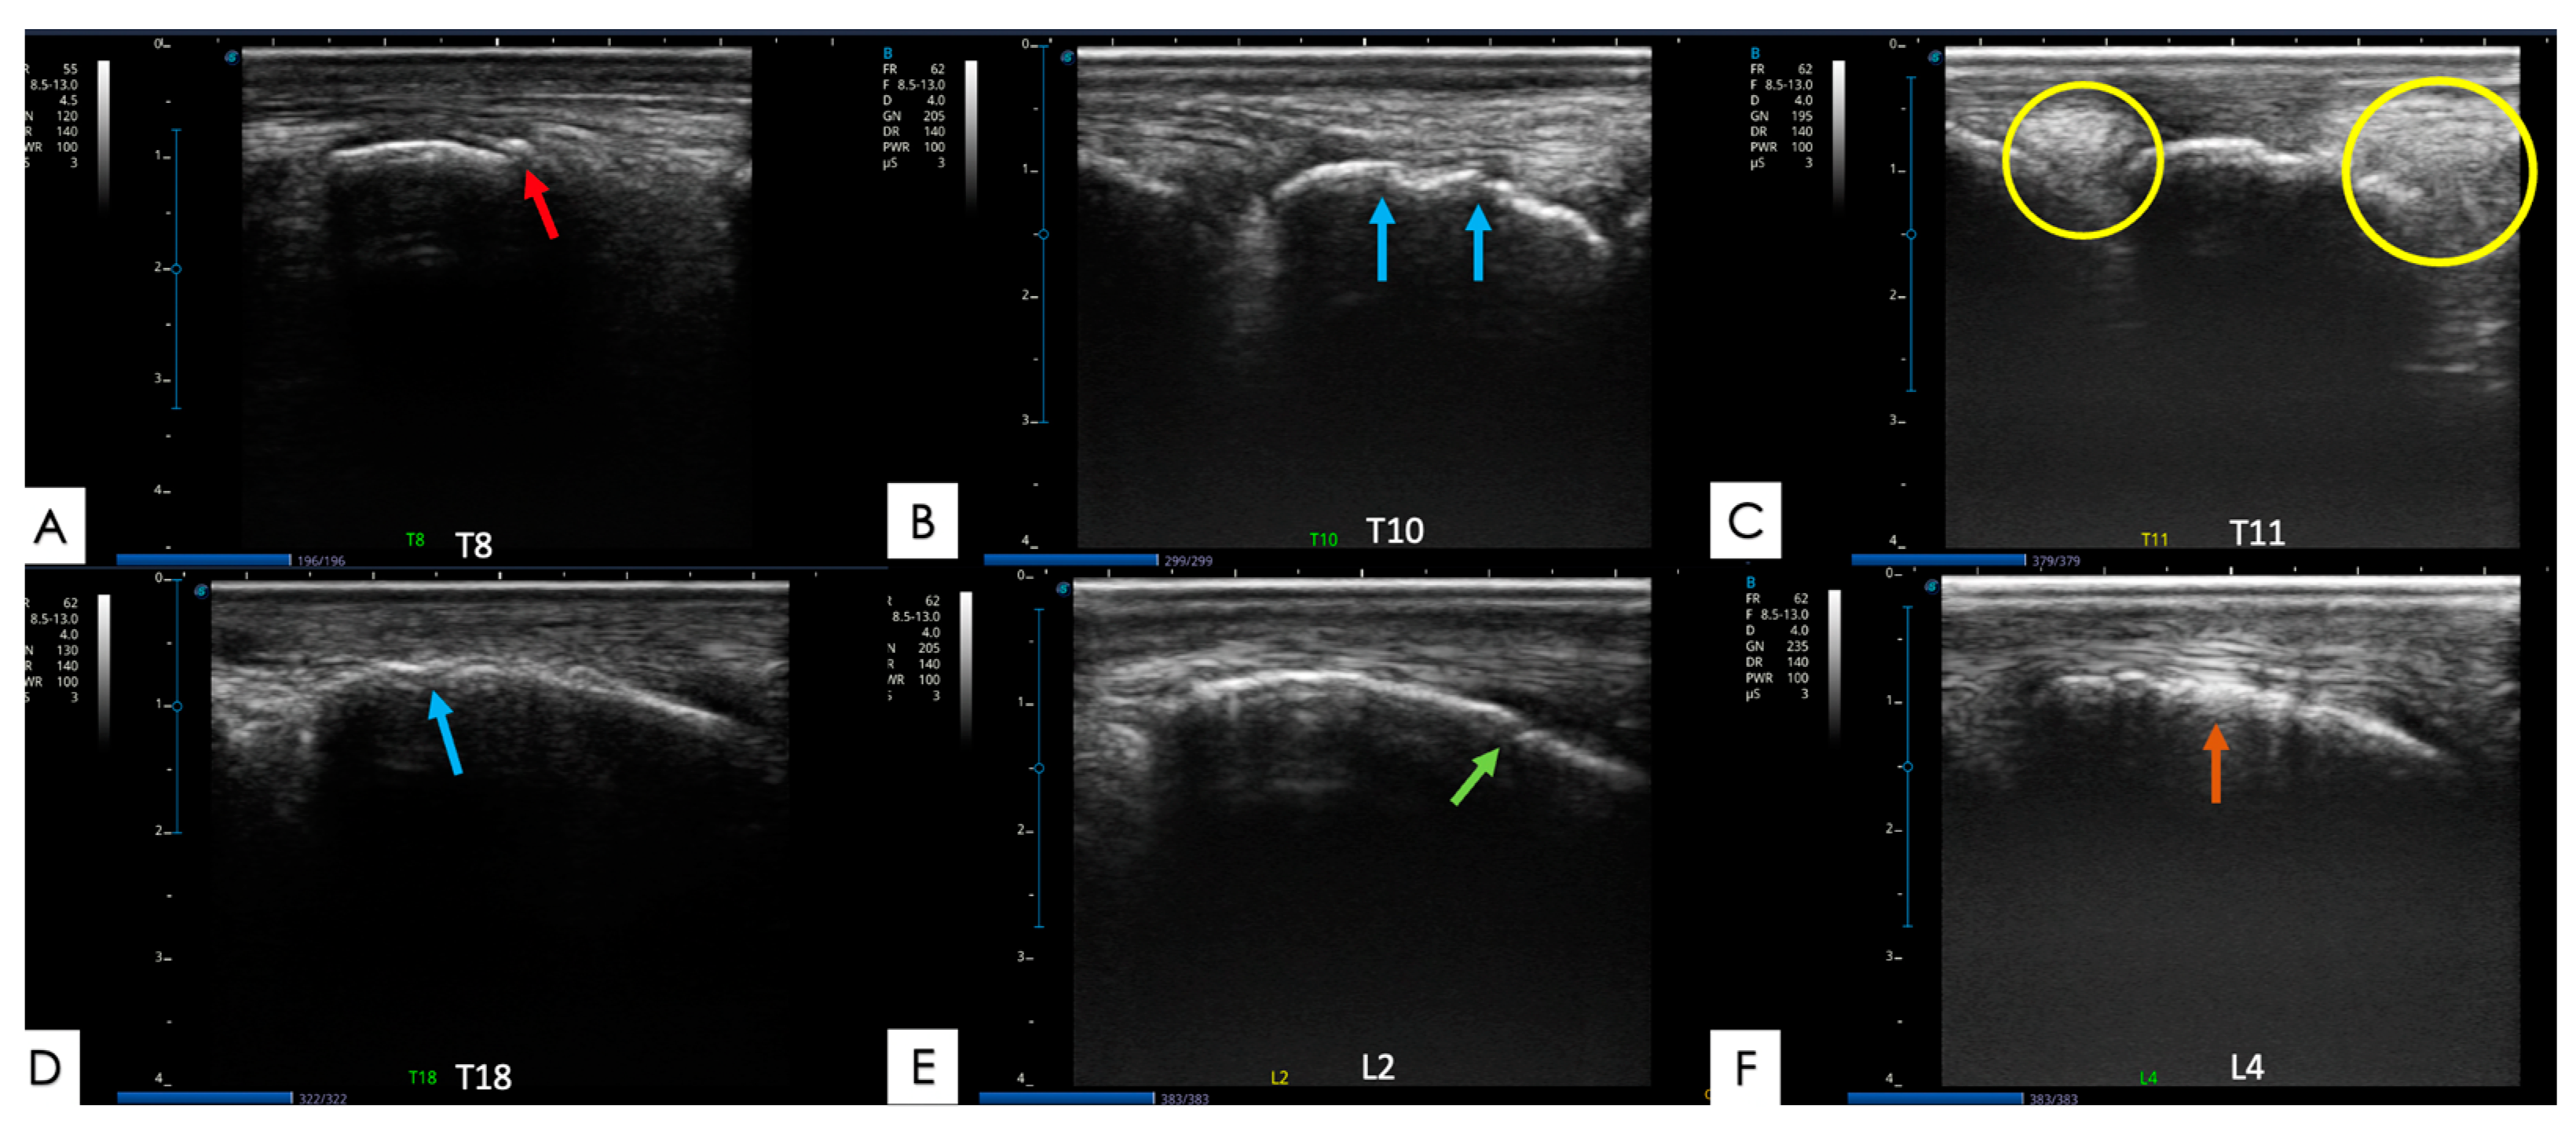

2.5.1. Articular Processes and Epaxial Muscle

2.5.2. Spinous Processes and Supraspinous Ligament